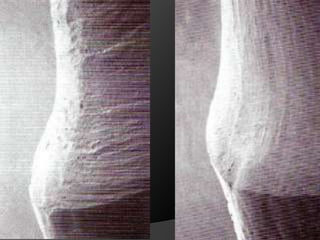

espesor biológico

fundamentos de periodoncia en prótesis fijaCuando, por la evolución de lesiones de caries, fracturas, o necesidad de ganancia de retención mecánica en pilares muy cortos, el espacio biológico es violado, existe la necesidad de restablecer sus dimensiones, como una forma de recuperar la salud del periodonto y de facilitar los procedimientos protésicos

fundamentos de periodoncia en prótesis fijaCirugía de Alargamiento CoronalExtrusión OrtodónticaTécnica Combinada